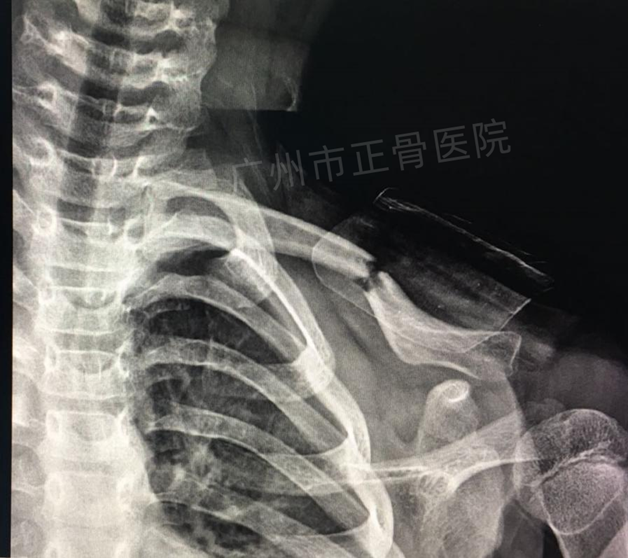

治疗:运用正骨手法复位后小夹板外固定治疗。复位后复查X线片提示骨折端对位对线明显改善。给予三角巾悬吊患肢,指导患者适当功能锻炼。4周后复查X线提示骨痂生长,骨折端稳定,予拆除夹板,检查患者肩关节活动正常。4个月后复查X线,骨性愈合。

▲4周后,骨痂生长